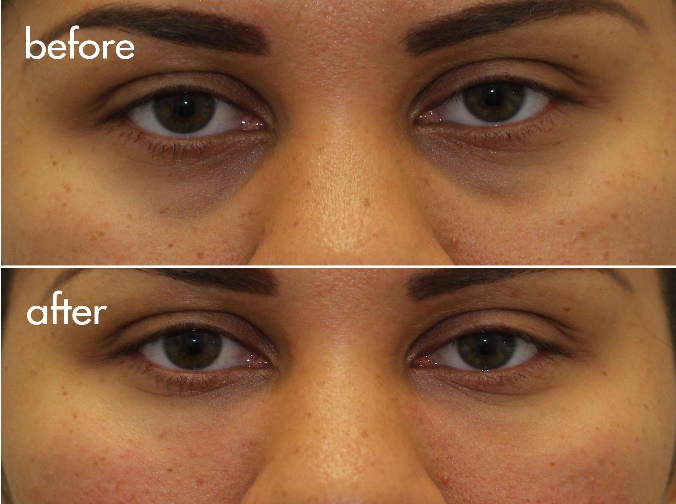

ویدیو تغییر شگفتانگیز: قبل و بعد از تزریق

برای مشاهده نتایج شگفتانگیز تزریق زیر چشم توسط دکتر احمدی، میتوانید ویدیوی قبل و بعد از تزریق را در [لینک ویدیو] مشاهده کنید. در این ویدیو، میتوانید تغییرات چشمگیر در ظاهر بیماران پس از انجام تزریق را مشاهده کنید.

دیدن این تغییرات میتواند به شما در تصمیمگیری بهتر کمک کند و انتظارات واقعبینانهای از نتایج این روش داشته باشید.